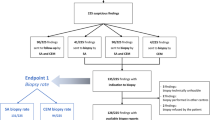

Follow-up surveillance episodes

Until the end of 2022 there were 2,592 subsequent surveillance episodes for analysis (Fig. 1), including at least two episodes for 1,065/1,190 (89%) patients and at least three episodes for 938/1190 (79%) (Table 2). After the first CEM, 93% of subsequent surveillance imaging was contrast based (CEM and/or MRI). Reasons for imaging without contrast included patient choice, previous contrast reaction (4 patients, mild reactions), untreated hyperthyroidism, contrast extravasation and a worldwide contrast shortage in mid-2022. The median time between surveillance episodes was 12 months (interquartile range, IQR, 11–12 months).

Study Flowchart, including key outcomes reported separately for first and subsequent round CEM surveillance. Combined figures are reported in various tables. DCIS ductal carcinoma in situ, CEM contrast-enhanced mammography, CDR cancer detection rate, FP false positive, PPV1 positive predictive value of any recall PPV3 positive predictive value of recalls resulting in biopsy, R round. aInterval cancer rate defined as interval cancers per 1000 surveillance episodes detected following one surveillance episode and before the next scheduled surveillance episode

Within the subsequent surveillance episodes, there were 116/2592 recalls (4.5%) of which 40/116 (34%) were TP and 76/116 (66%) were FP. The CDR was 15.4 per 1000 surveillance episodes, with PPV1 34% and PPV3 49% (Table 3).